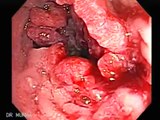

http://www.utmist.com/colorectal.html - If you are experiencing rectal bleeding, you should definitely have it checked to ensure it's not colon cancers. A specialist can determine if the rectal bleeding is caused by cancer or the lesser intestinal conditions involving hemorrhoids or diverticulitis. A specialist should be able to provide you with the proper treatment if it is actually a hemorrhoid case or a different condition.